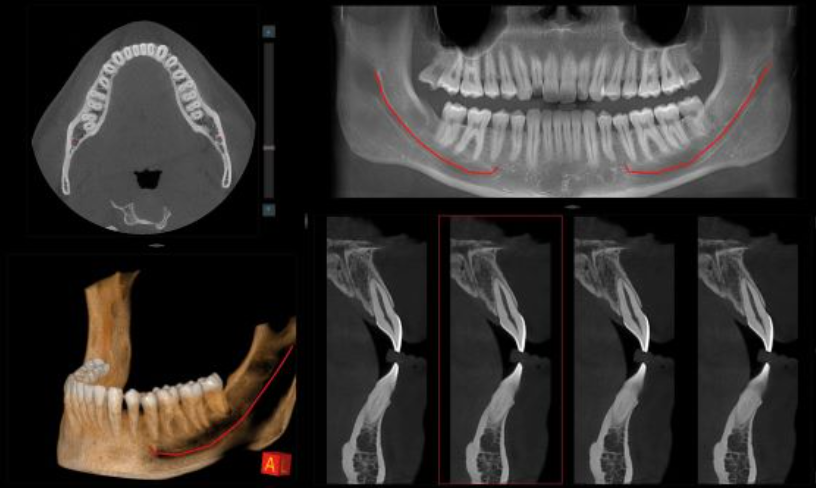

CBCT Cráneo Completo

Newton Giano

Sistema CBCT Newton Giano, líder en el sector de la radiología dental. Esta tecnología de  nos permite realizar diagnósticos detallados y precisos gracias a su capacidad para obtener imágenes tridimensionales de alta calidad del cráneo completo. Esto es fundamental no solo para la planificación y ejecución de tratamientos de implantología dental, sino también para la evaluación integral de la salud oral y general de nuestros pacientes.

Ubicación precisa del implante

Colocar implantes completamente rodeados de hueso asegura su durabilidad y estabilidad